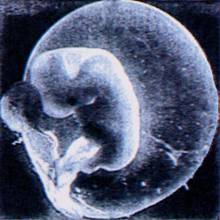

La procreazione assistita è una modalità di riproduzione operata dall'uomo per ottenere, in ambito zootecnico, individui con particolari caratteristiche e, in ambito medico, per superare ostacoli naturali che impediscono la fecondazione fisiologica in coppie che desiderano un figlio. La procreazione assistita comprende diverse tecniche, ciascuna delle quali viene applicata per rispondere a specifiche esigenze.

Gli ovociti che si sono normalmente fertilizzati, vengono mantenuti in coltura, cioè in un ambiente di crescita adeguato, per ulteriore 24-48 ore. Durante questo periodo essi cominciano le primissime fasi dello sviluppo, andando incontro a 1-3 divisioni cellulari e dando origine a pre-embrioni, ciascuno formato da 2-8 cellule.

Questa fase ha lo scopo di cercare di individuare i pre-embrioni con la più elevata capacità di sviluppo, individuando determinate caratteristiche morfologiche e il ritmo di divisione cellulare.

- IL TRASFERIMENTO DI PRE-EMBRIONE

A 48-72 ore dal prelievo degli ovociti, due o tre pre-embrioni scelti tra quelli di migliore qualità, vengono trasferiti nella cavità uterina della paziente. In questo modo è possibile aumentare le probabilità di ottenere una gravidanza in un determinato ciclo di trattamento, anche se aumenta parallelamente la possibilità di una gravidanza bi- o trigemellare. Il buon esito del trattamento non dipende esclusivamente dalla qualità degli embrioni, ma anche dalla capacità dell'utero di accoglierli. Trascorse circa due settimane dal trasferimento, il risultato del trattamento viene in un primo momento evidenziato tramite il dosaggio di un ormone prodotto dall'embrione che si è impiantato.